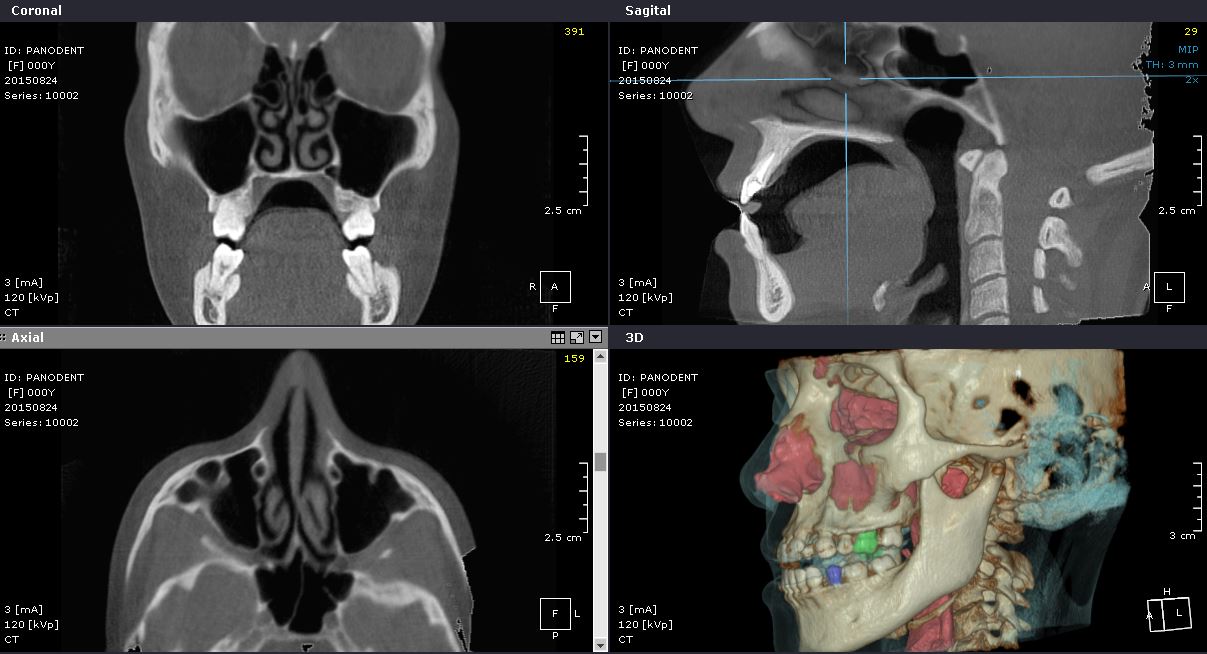

La CBCT (Tomografía Computarizada de Haz Cónico) ha creado una revolución sin precedentes en el campo dento-maxilofacial al pasar del diagnóstico dental 2D al 3D, expandiendo así el papel de la imagen diagnóstica a una guía visual de procedimientos quirúrgicos mediante el uso de un software.

Panodent está equipado con la más avanzada tecnología para ofrecer los servicios en Radiología de alta definición, necesarios para la nueva Odontología Digital, permitiendo al profesionista planificar cada tratamiento en las mejores condiciones, y poder ofrecer la máxima Precisión y Calidad diagnóstica.